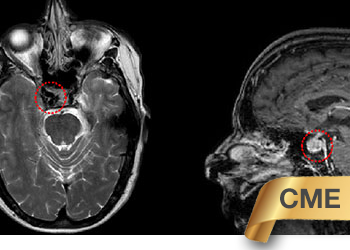

A 60-year-old woman who is otherwise healthy who presented with progressive right-sided pulsatile tinnitus for 4-6 weeks. She underwent extensive evaluation by her PCP and ENT […]

Examination: Her general and neurological examinations were normal. She was alert and oriented. Her cranial nerves were intact and her motor and sensory examinations were normal. […]